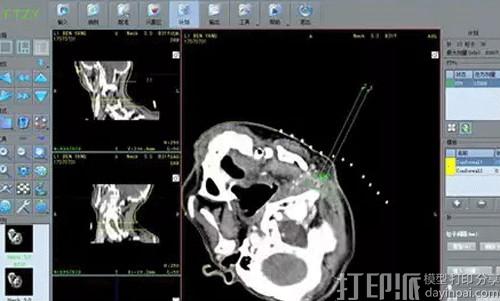

3D打印个体化模板将患者术前定位时的医学影像数据输入放射性粒子植入近距离治疗计划系统,为其量身定制出与其解剖结构、穿刺进针路径相匹配的个性化“非”共面引导模板。术前准备到手术结束只需3-5天。近日,威海市立医院杨福俊博士带领团队自主设计开展了3D打印模板立体空间引导技术,成功完成烟威首例3D打印技术下的“私人订制”近距离放疗。

3D打印模板技术为每位患者“量身定制”,在确保靶区剂量分布满意的前提下,可成功避开血管、骨骼、肠管等器官,实现精准复位、精准穿刺,精准植入,达到术前计划与术中实施的高度吻合。大幅减少了CT扫描的次数,缩短了手术时间,提高了精准度,显著减少了不必要的辐射剂量。

接受此次手术的是一位年近80岁的鼻咽癌根治性放疗后颈部高危区域淋巴结转移患者。杨福俊指出,因为患者年龄大,且属于复发的实体恶性肿瘤,按传统徒手穿刺植入,耗时预计达两到三个小时,术后验证与术前计划也可能存在偏差。实施3D打印个体化非共面模板辅助下恶性肿瘤放射性粒子植入术,将缩短一半以上的时间,大大提高植入精度,患者家属欣然接受此建议。手术耗时一个多小时,术后验证与术前计划几乎一致,目前患者恢复状况良好。